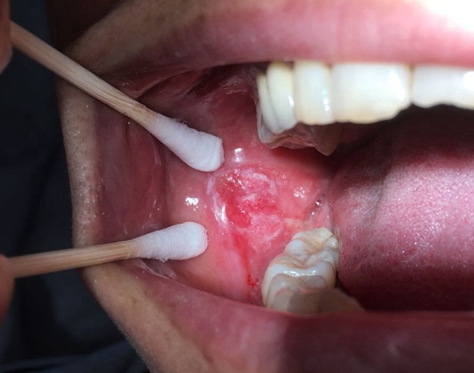

陈女士的右颊部“溃疡”

癌性溃疡,是口腔癌的一种临床表现形式,一般发生于老年患者,溃疡深浅不一,周围质硬有浸润,边缘不齐隆起翻卷,底部常呈菜花状细小颗粒突起,触摸底部有硬结,疼痛不明显,易与其他溃疡混淆。

而癌性溃疡一个很大的特征就是溃疡不能自愈,超过一个月还没有自愈的溃疡就必须到正规医院颌面外科找专科医生检查了。癌性溃疡多以单个出现为主,生长较快,形态类似于火山口状,溃疡边缘一般有隆起发硬,后期还会伴有出血等表现。